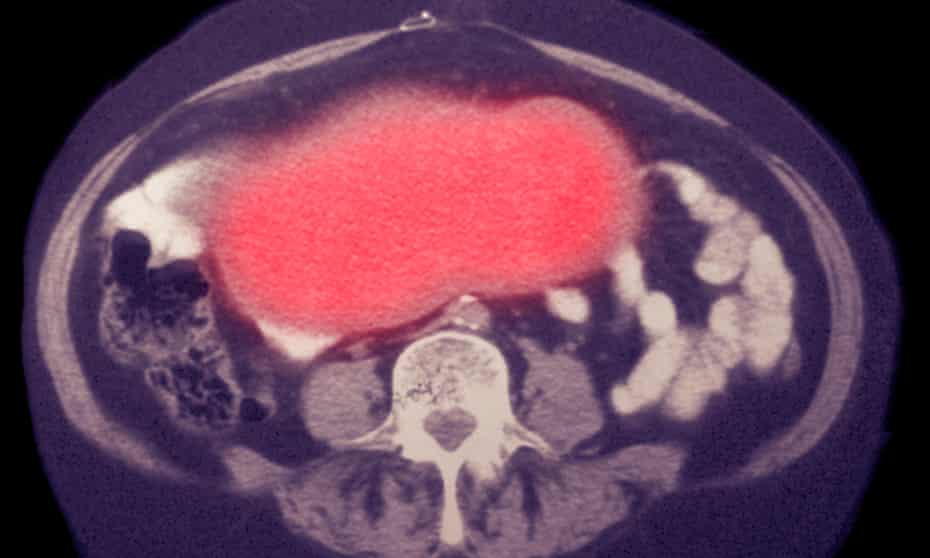

Ο καρκίνος των ωοθηκών ευθύνεται για το μεγαλύτερο ποσοστό θανάτων από γυναικολογικούς καρκίνους, καθώς στο 75% των περιπτώσεων – τρεις στις τέσσερις – διαγιγνώσκεται σε καθυστερημένο στάδιο, όταν πια οι όγκοι έχουν εξαπλωθεί.

Οι ερευνητές χρησιμοποίησαν δείγματα κυττάρων από 242 γυναίκες με καρκίνο των ωοθηκών και 869 χωρίς, εντοπίζοντας τελικά – με τη βοήθεια τεχνητής νοημοσύνης – μια μοναδική «υπογραφή» DNA που μπορεί να αξιοποιηθεί για να γίνει ανίχνευση του καρκίνου ή πρόγνωση ότι θα εμφανιστεί στο μέλλον.

Το τεστ «έπιασε» το 71,54% των γυναικών έως 50 ετών και το 54,5% των γυναικών άνω των 50 ετών που είχαν καρκίνο των ωοθηκών.